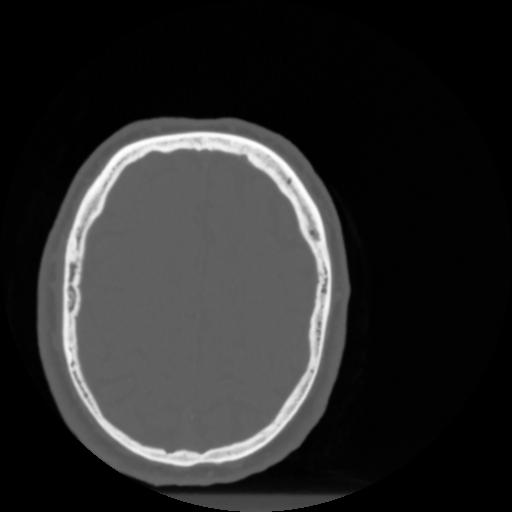

4 CEREBRO,,Vol,0.5,CEREBRO,,